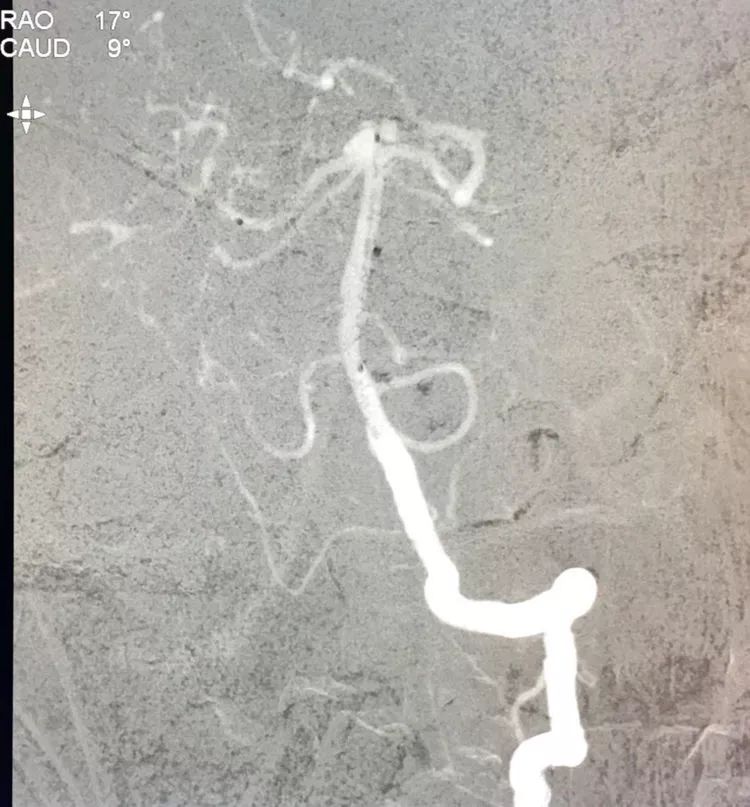

左椎动脉工作位路图

Sychro14微导丝携Headway21支架导管经左椎动脉-基底动脉进入右侧PCA,因瘤颈主要累及右侧PCA,故计划支架跨基底动脉顶端动脉瘤释放于右侧PCA-基底动脉内。

Echelon10(直头)微导管用Sychro14微导丝引入瘤腔内。

先送入一段弹簧圈

将LVIS支架(3.5×15)跨瘤颈释放于右侧PCA-基底动脉内